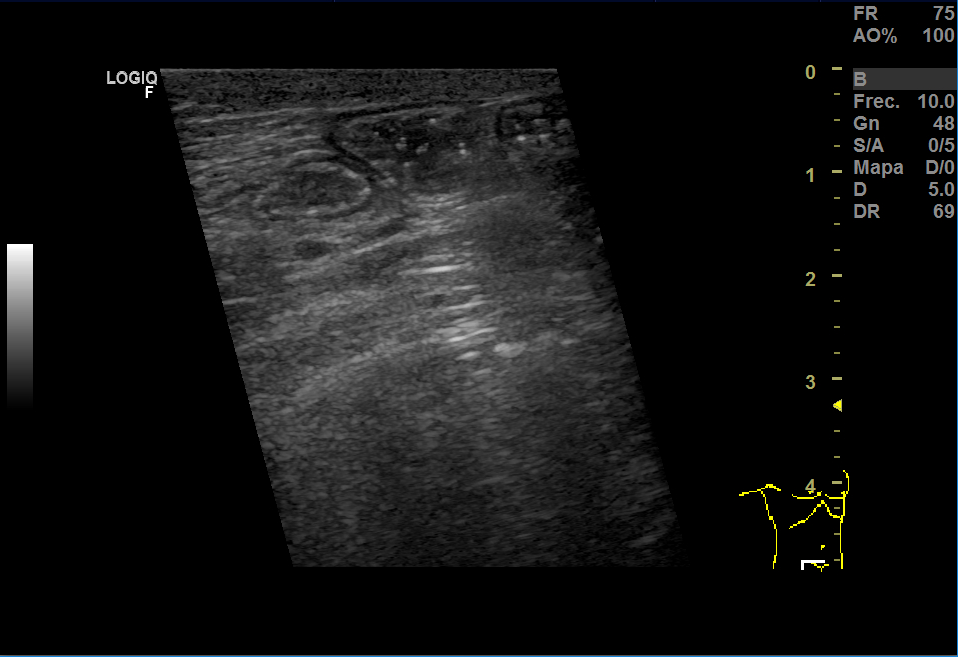

Realizamos una ecografía en Centro de Salud donde vimos que había una herniación derecha y aumento del grosor del tejido celular subcutáneo y, en el espesor, una imagen anecoica que no sabíamos bien a qué podía corresponder.

En la urgencia, realizaron una analítica y encontraron 14.600 leucocitos, PCR 5,13. En Eco testicular, se apreciaron testes de ecoestructura y ecogenicidad normales, epidídimos normales y aumento del grosor del TCSC que impresionaba de celulitis y, en el espesor, una pequeña colección de 15 mm que podía corresponder a absceso o hematoma.